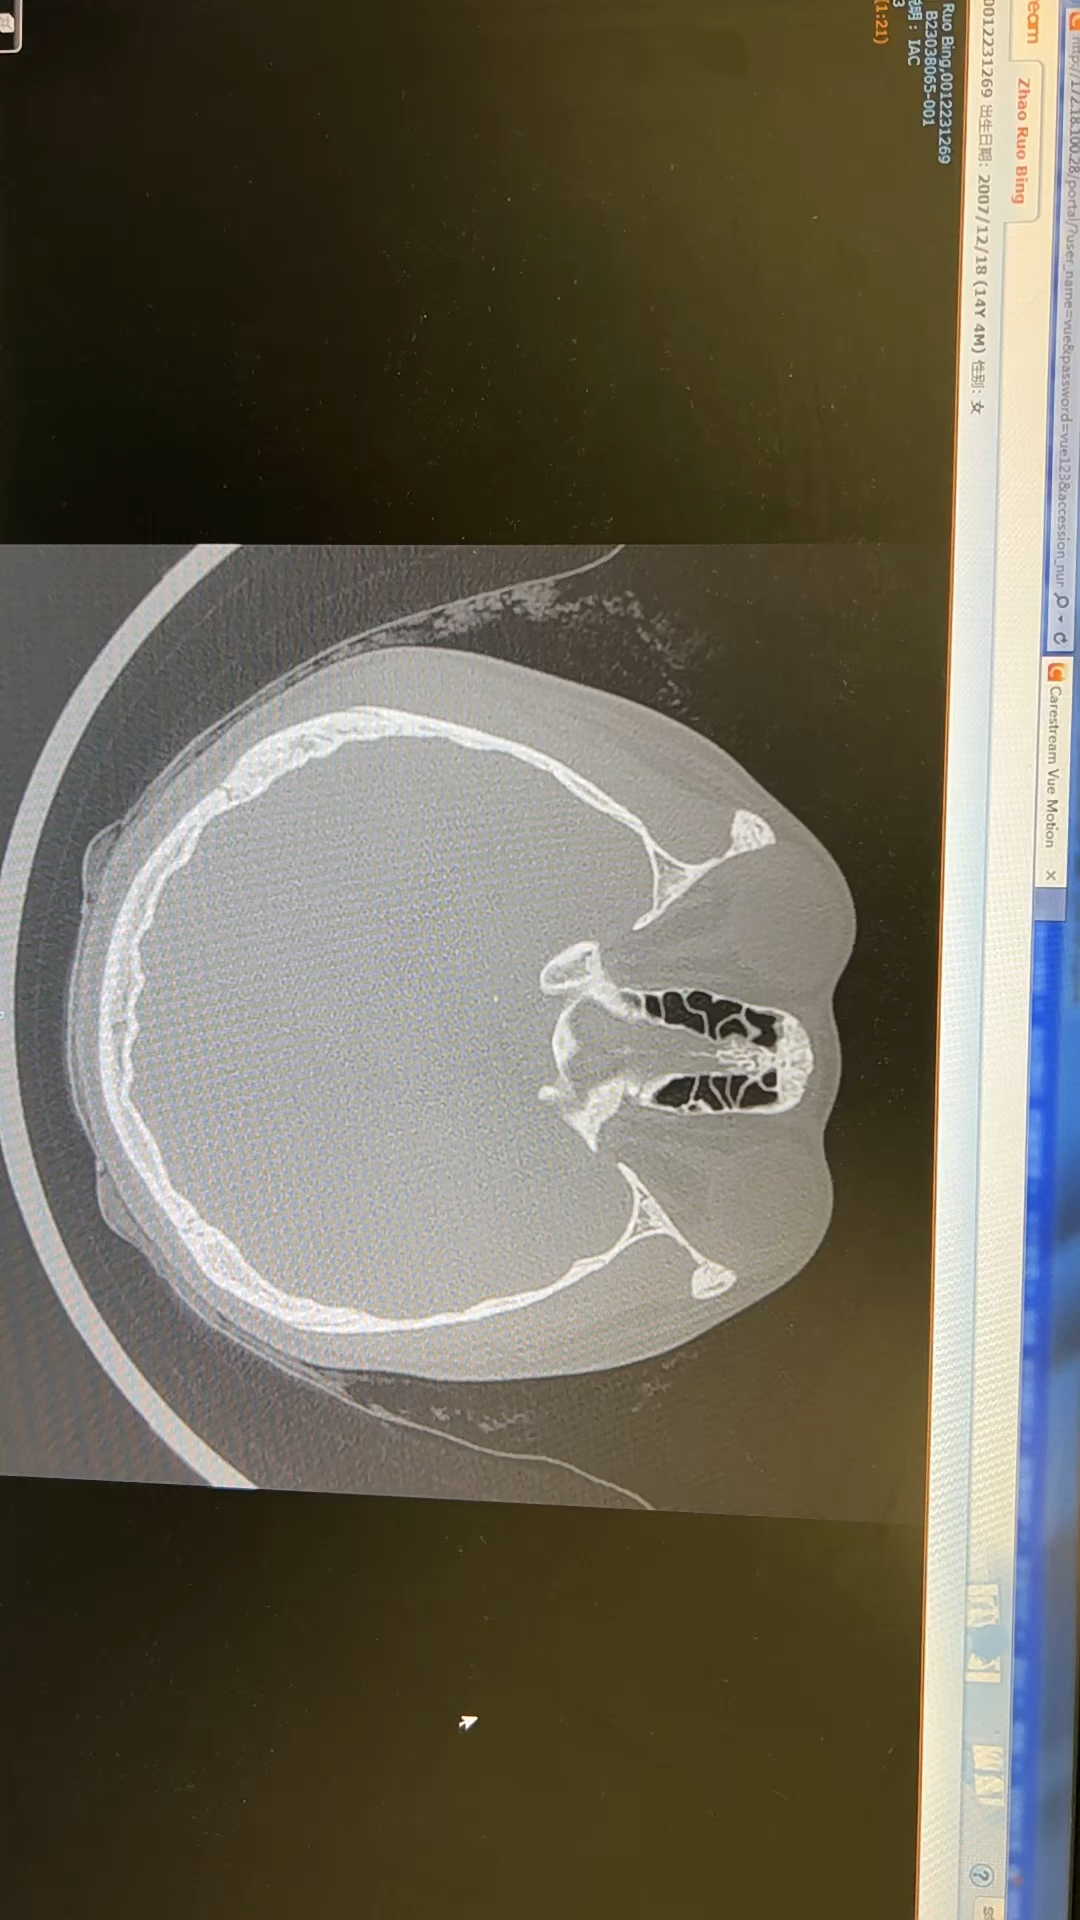

中耳胆脂瘤一例

图片尺寸512x512